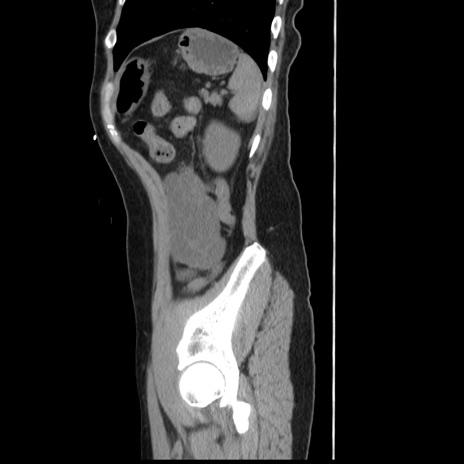

冠状断像

【症例】 50歳代女性

【主訴】 腹痛

【現病歴】前日生レバーを食べた。今朝に排便あり。 昼前に突然発症の腹痛を生じ、当院救急外来を受診した。

【既往歴】 子宮筋腫にてで子宮全摘後

【身体所見】 意識清明、腹部:平坦、軟、下腹部やや左を中心に圧痛・反跳痛あり、筋性防御あり

【データ】WBC 7800、CRP 0.07